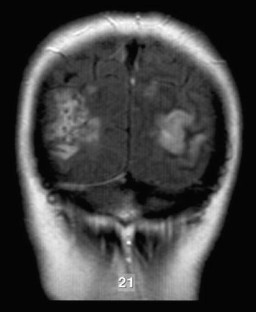

Extinction limited to visual motion perception in the left hemifield was demonstrated. The visual defect was attributed to a lesion involving the right occipito-temporo-parietal region in the presence of a left posterior infarction.

Fig 1